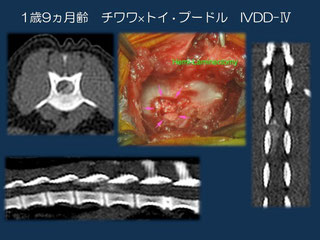

椎間板疾患(Intervartebral disc disease:IVDD)

椎間板ヘルニアとは脊椎の間にあるクッションの一部が飛び出し、脊髄神経を圧迫することで、様々な症状を引き起こします。痛み、しびれ、麻痺などが起こります。

ただし、歩けない状態や尻尾を振ることが出来ない状態、痛覚を失ってしまっている場合には脊髄造影、CT、MRIなどの精密検査ののち病気の場所を特定し、できるだけ早く外科手術を行います。症状が重い状態で、鍼治療などを優先することは避けたほうが良いでしょう。

片側椎弓切除術

ミニへミラミネクトミー

コルペクトミー

腹側減圧術

尾側頚椎の背側椎弓切除術

主に頚椎の椎間板ヘルニアの際に行われます。